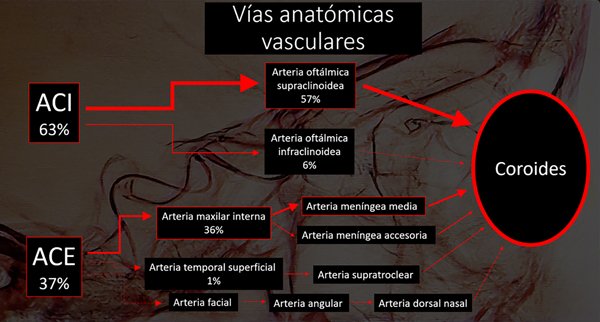

Entre junio 2010 y hasta junio 2021 fueron realizadas 820 sesiones en 176 pacientes (4.6 sesiones por paciente). Todas las intervenciones fueron realizadas por dos neurorradiólogos intervencionistas especialistas. En todos los casos la arteria oftálmica pudo ser cateterizada, 535 directamente (63%) y 285 por vía arteria meníngea media (o meníngea accesoria) con una opacificación coroidea óptima (fig. 1). La principal vía vascular utilizada es la arteria oftálmica con un nacimiento distal al anillo dural (supraclinoidea). De no estar presente o de no poder obtener una correcta opacificación de la coroides por este acceso utilizamos ramos de la arteria carótida externa. La anastomosis entre la arteria meníngea media y la arteria oftálmica está ampliamente descripta en la literatura. Esta comunicación puede darse directamente o a través de la arteria lagrimal o la arteria supraorbitaria. La arteria temporal superficial excepcionalmente puede dar una anastomosis a través de la arteria supratroclear. En nuestra experiencia pudimos corroborar además la existencia de anastomosis entre la arteria meníngea accesoria y la arteria oftálmica, y entre la arteria facial, a través de la arteria angular con la arteria dorsal nasal. La arteria carótida externa es una vía alternativa de gran utilidad ya que presenta múltiples vías de comunicación que pueden ser utilizadas7.

Fig 1: Distribución de las principales vías anatómicas vasculares para quimio-infusión. ACI: Arteria carótida interna. ACE: Arteria carótida externa. El grosor de las flechas es proporcional al orden de frecuencia